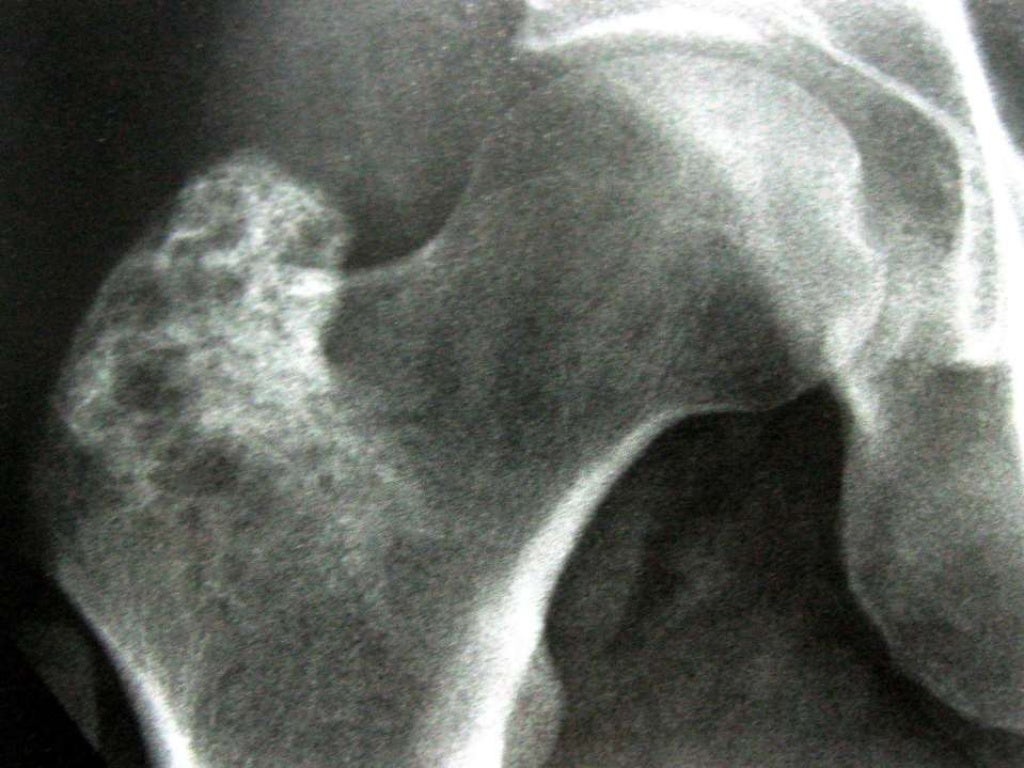

METÁSTASE PARA OS OSSOS NO PACIENTE COM CÂNCER Oncologia Ortopédica